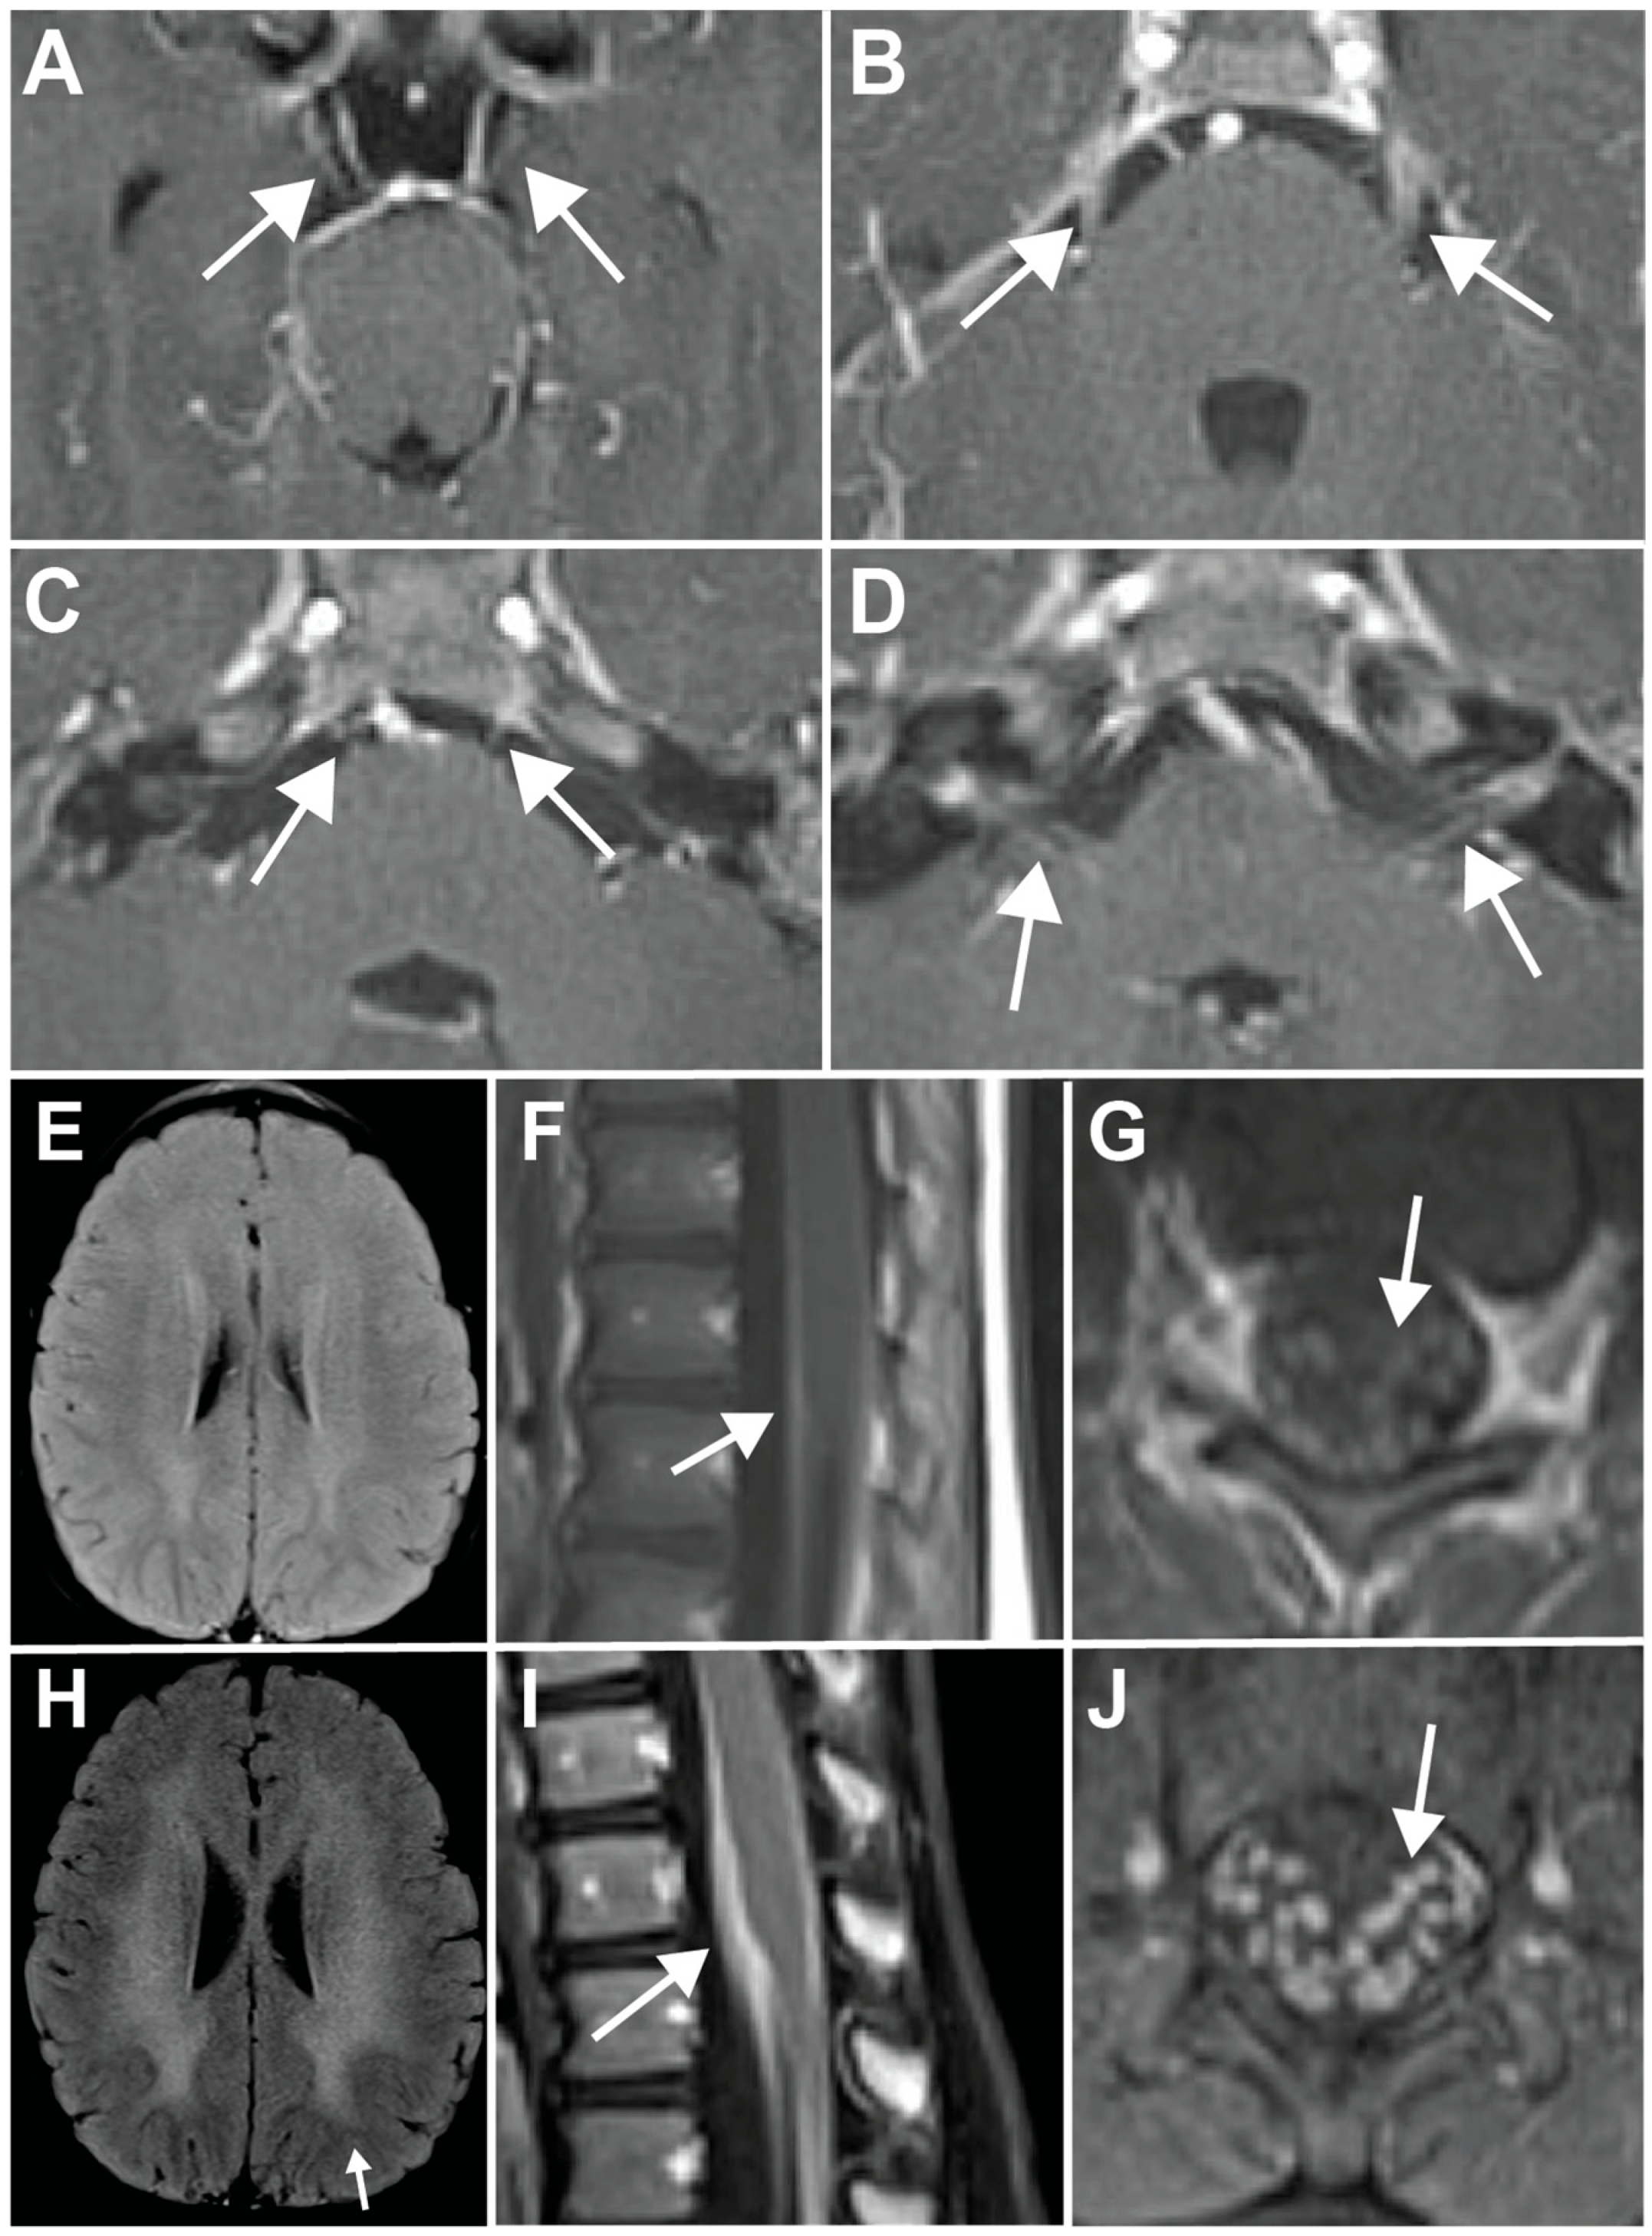

Metachromatic Leukodystrophy Presenting with Multiple Cranial Nerve and Lumbosacral Nerve Root Enhancement Without White Matter Changes

Jauregui, R.; Garcia, M.R.; Mehuron, T.; Galetta, S.L.; Segal, D. Metachromatic Leukodystrophy Presenting with Multiple Cranial Nerve and Lumbosacral Nerve Root Enhancement Without White Matter Changes. Neurol. Int. 2025, 17, 28. https://doi.org/10.3390/neurolint17020028